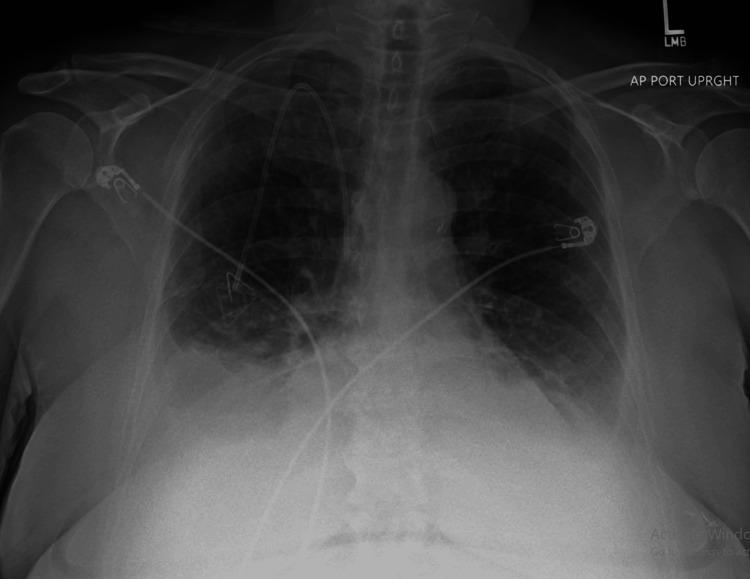

Imatinib, a tyrosine kinase inhibitor, is widely used for treating gastrointestinal stromal tumors (GISTs) and chronic myeloid leukemia (CML). While commonly associated with mild fluid retention, significant pleural effusion is an uncommon but potentially serious adverse effect. We present a case of recurrent pleural effusions secondary to imatinib therapy in a 62-year-old female patient with metastatic lung adenocarcinoma and a concurrent GIST harboring an exon 9 mutation. She was initiated on imatinib 400 mg daily, later increased to twice daily. Within weeks, she developed progressive dyspnea, and imaging revealed large bilateral pleural effusions. Pleural fluid analysis demonstrated an exudative effusion, with cytology and microbiological studies ruling out infection or malignancy. Cardiac function was preserved, and there were no signs of volume overload. She underwent multiple thoracenteses for symptomatic relief. Due to recurrent pleural effusions, imatinib was permanently discontinued, leading to complete resolution of the effusions. Subsequent treatment with sunitinib was not tolerated due to severe mucositis and cytopenias. Despite discontinuation of targeted therapy, both her GIST and metastatic lung cancer remained stable under surveillance. While pleural effusions are frequently reported with dasatinib, they are rare with imatinib. The proposed mechanisms include inhibition of platelet-derived growth factor receptors (PDGFRs), leading to increased vascular permeability, impaired lymphatic drainage, and renal sodium retention. Dose reduction may mitigate fluid retention; however, our patient developed significant pleural effusions at standard dosing, necessitating treatment discontinuation. This case underscores the importance of recognizing pleural effusion as a rare but serious adverse effect of imatinib therapy. Clinicians should maintain a high index of suspicion for drug-induced pleural effusions, particularly in the absence of other etiologies, and consider discontinuation if clinically indicated. Early recognition and management can prevent complications and improve patient outcomes.

伊马替尼是一种酪氨酸激酶抑制剂,广泛用于治疗胃肠道间质瘤(GIST)和慢性粒细胞白血病(CML)。虽然通常与轻度液体潴留有关,但大量胸腔积液是一种罕见但可能严重的不良反应。我们报告一例62岁女性患者,患有转移性肺腺癌和同时存在外显子9突变的GIST,因伊马替尼治疗继发反复胸腔积液。她开始每天服用400毫克伊马替尼,后来增加到每天两次。几周内,她出现进行性呼吸困难,影像学检查显示双侧大量胸腔积液。胸腔积液分析显示为渗出性积液,细胞学和微生物学研究排除了感染或恶性肿瘤。心脏功能保持正常,没有容量超负荷的迹象。她接受了多次胸腔穿刺以缓解症状。由于反复出现胸腔积液,伊马替尼被永久停用,积液完全消退。随后使用舒尼替尼治疗因严重粘膜炎和血细胞减少而无法耐受。尽管停用了靶向治疗,但在监测下她的GIST和转移性肺癌均保持稳定。虽然达沙替尼经常报告有胸腔积液,但伊马替尼引起的则很少见。推测的机制包括抑制血小板衍生生长因子受体(PDGFR),导致血管通透性增加、淋巴引流受损和肾钠潴留。减少剂量可能减轻液体潴留;然而,我们的患者在标准剂量下出现了大量胸腔积液,需要停药。该病例强调了认识到胸腔积液是伊马替尼治疗罕见但严重的不良反应的重要性。临床医生应高度怀疑药物性胸腔积液,特别是在没有其他病因的情况下,并在临床指征明确时考虑停药。早期识别和管理可以预防并发症并改善患者预后。